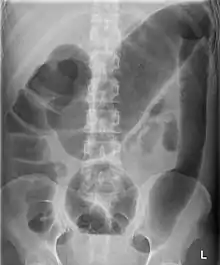

| Toxic megacolon associated with ulcerative colitis. | |